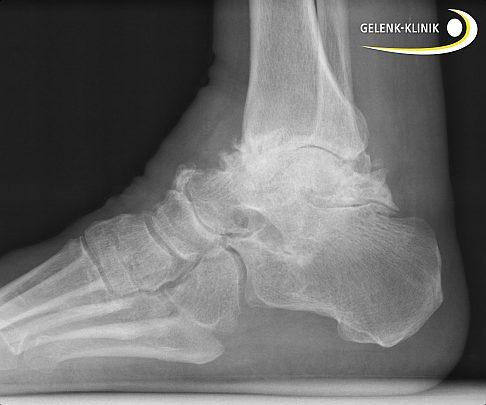

Die Sprunggelenksarthrose hat jedoch meist traumatische Ursachen. Das bedeutet, ein Unfall, eine Sprunggelenksfraktur oder ein verrenkter Knöchel verursachen eine Schädigung der Bänder. Dieses Trauma legt die Grundlage für den vorzeitigen Verschleiß des Sprunggelenks.

Weiterhin können Knochensporne (Osteophyten) an der vorderen Schienbeinkante zu Knorpelschäden im Sprunggelenk führen. Auch avaskuläre Osteonekrosen (Knochentod) wie die Osteochondrosis dissecans (OD) sind häufig Auslöser für eine Schädigung der Gelenkfläche. Hierbei stirbt der unter dem Knorpel liegende Knochen aus unbekannter Ursache ab, sodass die Knorpelschicht letztendlich in den entstehenden Knochendefekt einbricht.